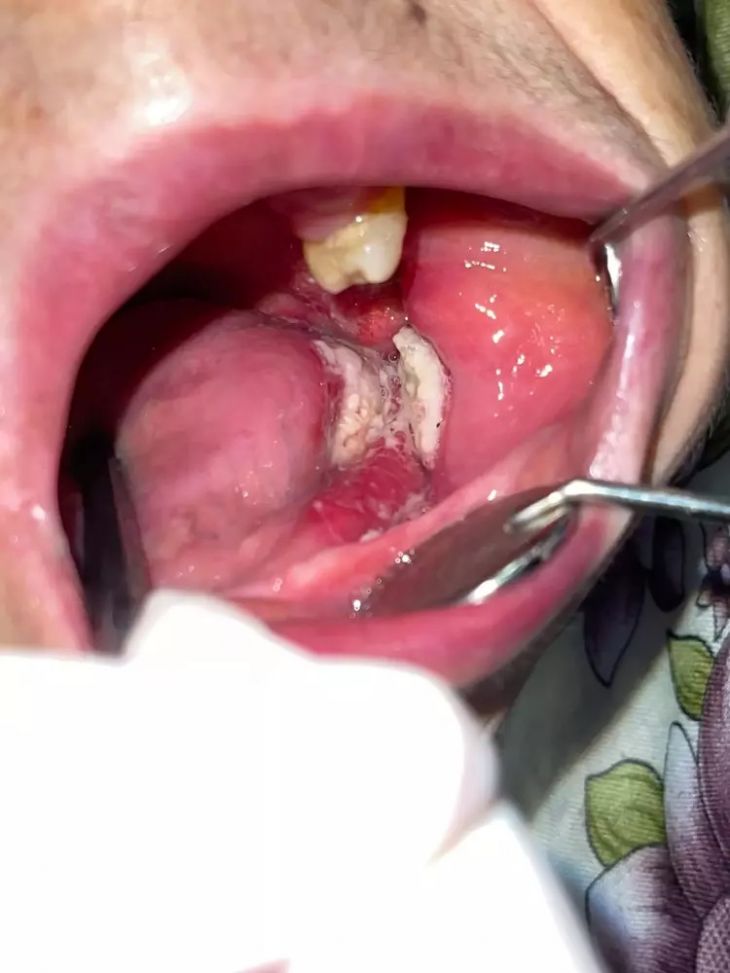

OMÜ Diş Hekimliği Fakültesi Dekanı Prof. Dr. Kaan Gündüz, vatandaşların ağız içi yaraları çoğu zaman önemsemediğini, tütün kullanımı, yetersiz ağız bakımı, güneş maruziyeti ve HPV virüsünün ağız kanserlerinin artışında etkili olduğunu ifade etti. Ağızda 2 haftadan uzun süren yaralar, sebepsiz diş sallanması, uyuşukluk ve çene ağrıları mutlaka dikkate alınması gerektiğini belirten Prof. Dr. Gündüz, ağız kanserinden korunma yolları arasında tütün ve alkol kullanımını azaltmak olduğunu belirtti. Prof. Dr. Gündüz, “Oral kanserler dediğimiz şey aslında başlangıçları çok hızlı ve sinsi gelişen durumlar. Bundan dolayı mutlaka hastaların 2 haftadan uzun süren ağızdaki yaraları eğer mevcutsa en yakın diş hekimlerine başvurmaları gerekmekte. En son yapılan, 2022 yılında Sağlık Bakanlığı yapmış oldu araştırmada 2 bin 246 tane ağız kanserine rastlanmış. Bu vakaların 551 tanesi ölümle sonuçlanmış. Bu da Türkiye kanser görülme olasılığını yüzde 1'ine tekabül ediyor ama şimdi şöyle bir durum var. Şimdi bizim insanlarımız kulağından bir damla kan gelince hemen işte gerekli doktora gider iken ağzından kan gelme durumunda çok fazla önemsemiyor. Yani ağız, dişler çok fazla önemsemiyor ne yazık ki. Ancak Özellikle son yıllarda artan tütün kullanımı ki bunun formasyonları var biliyorsunuz işte ne bileyim nargilesinden, piposundan, purosundan artmasından dolayı oral hijyenin, ağız bakımının eksikliğinden dolayı ve son yıllarda özellikle sizlerin de televizyonlarda veya işte bazı haber kanallarına duyduğunuz Human Papilloma Virüsü dediğimiz HPV'nin yaygınlaşmasından dolayı güneşe maruziyetinden dolayı insanlarda özellikle oral kanserler çok daha fazla sıklıkla görülüyor” diye konuştu.

Ağız kanserinde erken tanı gerçekleşirse hastaların ölümle sonuçlanmasının önüne geçilebileceğini ifade eden Prof. Dr. Gündüz, “Biz kurum olarak Karadeniz'in en büyük üniversitesiyiz ve de fakülte olarak da Karadeniz'de büyük bir hizmet vermekteyiz. Ortalama yaklaşık günde 500 hasta, aylıkta 10 bine yakın hasta bakıyoruz. Biz yapmış olduğumuz seminerlerde hem öğrencilerimizi hem asistanlarımızı hem de halkımızı bu konuda bilgilendirmeye çalışıyoruz. Erken tanı eğer gerçekleşirse bu hastalıkların ölümle sonuçlanmasının nispeten önüne geçmiş oluyoruz. Çünkü erken tanı biliyorsunuz her kanser vakasında çok önemli bir yer tutmakta. Herhangi birisi ağzında eğer 2 haftanın üzerine geçmeyen bir yara varsa mutlaka en yakın diş hekimine başvurması gerekmekte. Sebepsiz yere dişlerin sallanması, uyuşukluk olması, yüzde sebepsiz ağrıların, çene bölgesinde sebepsiz ağrıların oluşması kanserlerin başlangıç bulguları arasındadır. Zaten kanserlerin en fazla oluştuğu yerler ağız içerisinde dilin özellikle arka kenarlarıdır. Bunlar ne yazık ki başlangıçları da ağrısız olduğu için bir kısmının gözden kaçabilmekte. O yüzden insanlarımızdan, halkımızdan bu konuda dikkat etmeleri, eğer böyle bir lezyonla muhatap olurlarsa mesela bir yakınından ağız içerisindeki görüntüsünü çekmesini talep etmeli. 2 hafta sonra da aynı şekilde bu görüntü duruyorsa veya daha da büyümüşse en yakın merkeze gitmesini önermekteyiz” ifadelerini kullandı.